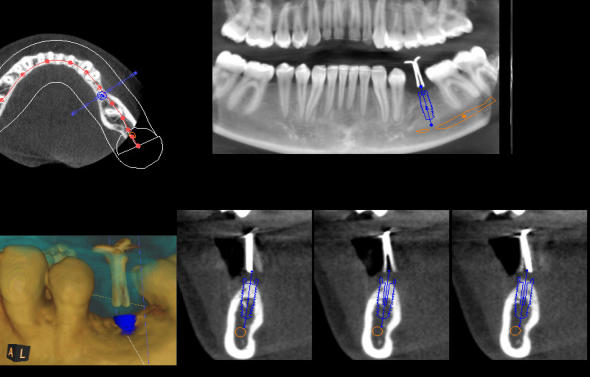

Die 3D-Röntgentechnik oder digitale Volumentomographie liefert 3-dimensionale Ansichten der Kiefer und der Zähne und ist ein großer Gewinn für die zahnärztliche Diagnostik. Bestimmte krankhafte Prozesse werden nur mit diesem Verfahren dargestellt. Häufig werden auch bisher versteckte Befunde entdeckt. Implantatplanungen können mit 3D-Röntgenaufnahmen präziser und vor allem sicherer vorgenommen werden. Exakte Vermessungen sind in diesen Ansichten möglich. Wurzelbehandlung (Endodontie) lassen sich sicher durchführen. Die 3D-Technik ermöglicht ein exaktes Erkennen der Wurzelanatomie, Lokalisieren und Vermessen der Wurzelkanäle. Parodontalbehandlungen (regenerative Parodontologie) lassen sich im Voraus planen. Dadurch kann die Behandlung gezielt und schonend durchgeführt werden. Weitere diagnostische Anwendungsgebiete der digitalen Volumentomographie liegen im Bereich der zahnärztlichen Chirurgie, z.B. für schwierige Weisheitszahnentfernungen, Lagebestimmungen von verlagerten Zähnen und Fremdkörpern.

Die 3D-Röntgentechnik oder digitale Volumentomographie liefert 3- dimensionale Ansichten der Kiefer und der Zähne und ist ein großer Gewinn für die zahnärztliche Diagnostik. Bestimmte krankhafte Prozesse werden nur mit diesem Verfahren dargestellt. Häufig werden auch bisher versteckte Befunde entdeckt. Implantatplanungen können mit 3D-Röntgenaufnahmen präziser und vor allem sicherer vorgenommen werden. Exakte Vermessungen sind in diesen Ansichten möglich. Wurzelbehandlung (Endodontie) lassen sich sicher durchführen. Die 3D- Technik ermöglicht ein exaktes Erkennen der Wurzelanatomie, Lokalisieren und Vermessen der Wurzelkanäle. Parodontalbehandlungen (regenerative Parodontologie) lassen sich im Voraus planen. Dadurch kann die Behandlung gezielt und schonend durchgeführt werden. Weitere diagnostische Anwendungsgebiete der digitalen Volumentomographie liegen im Bereich der zahnärztlichen Chirurgie, z.B. für schwierige Weisheitszahnentfernungen, Lagebestimmungen von verlagerten Zähnen und Fremdkörpern.